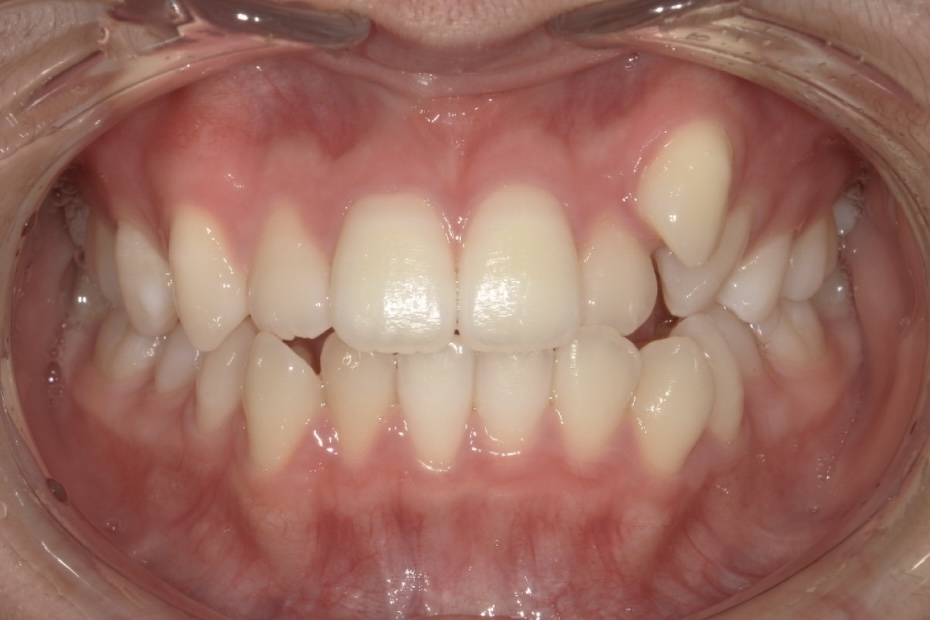

高校生女性 八重歯と噛み合わせが気になる

高校生の女性の患者さまで、初診時は15歳でした。八重歯と噛み合わせの乱れを主訴にご相談に来院されました。歯並びについて意識するようになったきっかけは、学校の歯科健診で矯正治療をすすめられたことだったそうです。

八重歯や噛み合わせが整い、口元の印象が大きく改善しています。治療後には、矯正中のモチベーション維持や経過確認がしやすかった点、想定よりも早く治療を終えられたことについて、嬉しい口コミもお寄せいただきました。

BEFORE

AFTER